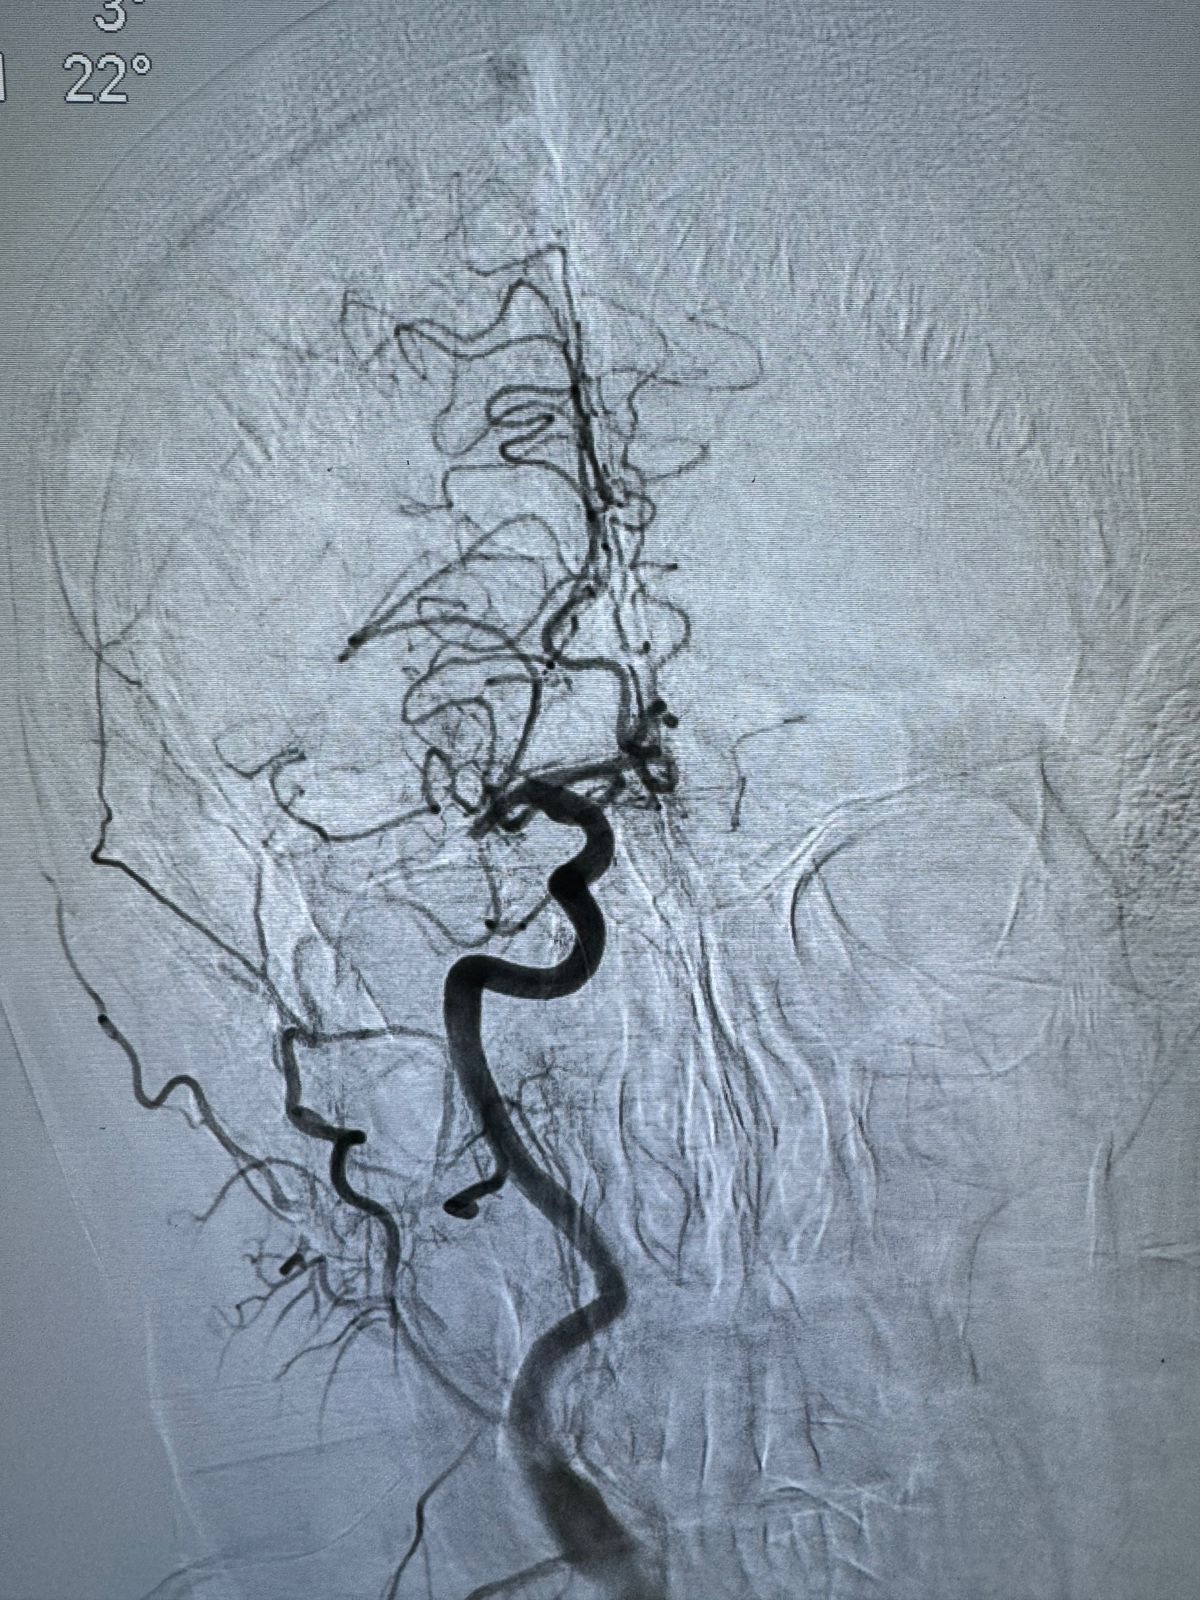

Бригада скорой помощи доставила пациентку в тяжелом состоянии с клиникой острого ишемического инсульта, с жалобами на слабость и онемение в левых конечностях. Кроме того, у женщины наблюдалась нечеткость речи. Специалисты диагностировали у женщины инфаркт мозга, вызванный эмболией артерий.

Пациентке экстренно провели операцию. Используя новую технологию, ей удалили тромбы.

«Это прогрессивный малотравматичный метод хирургического лечения. Он позволяет быстро и эффективно полностью восстановить кровоток мозговой артерии, значительно снижая последствия инсульта и улучшая прогноз пациента. Выполнять такую операцию могут лишь опытные и специализированные врачи, знающие до тонкостей анатомию сосудов головного мозга», – разъясняют специалисты.